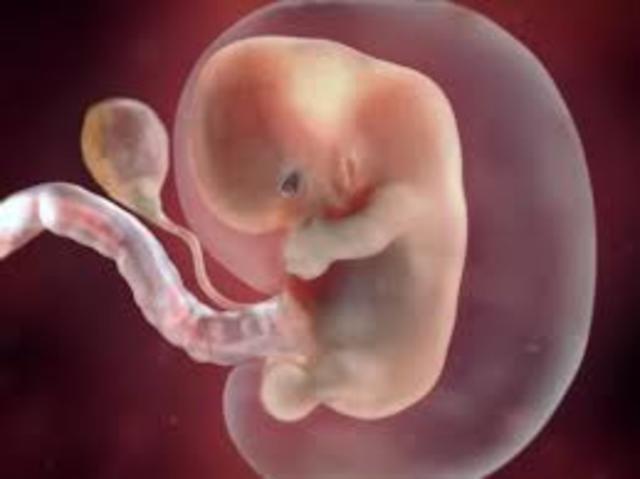

• development at 4 weeks

development at 4 weeks

baby developing structure that will eventually form is face and neck the heart and blood vessels continue to develop and the lungs stomach liver start to develop